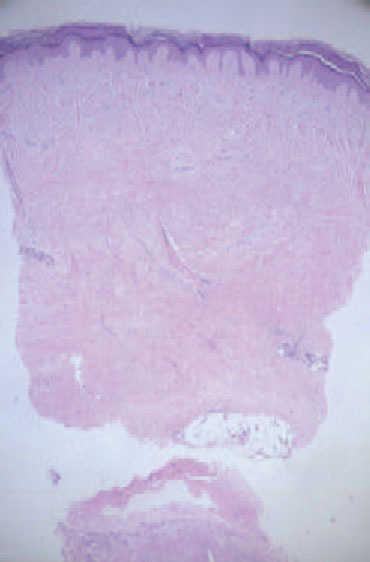

Se realizó una biopsia cutánea, en la que se evidenció un ensanchamiento de la dermis con haces de colágeno alargados y engrosados, atrapamiento de las estructuras anexiales y escasa celularidad (fig. 3).

Fig. 3.—Engrosamiento de la dermis con haces de colágeno alargados y gruesos, escasa celularidad y atrapamiento de estructuras anexiales. (Hematoxilina-eosina, ×25.)